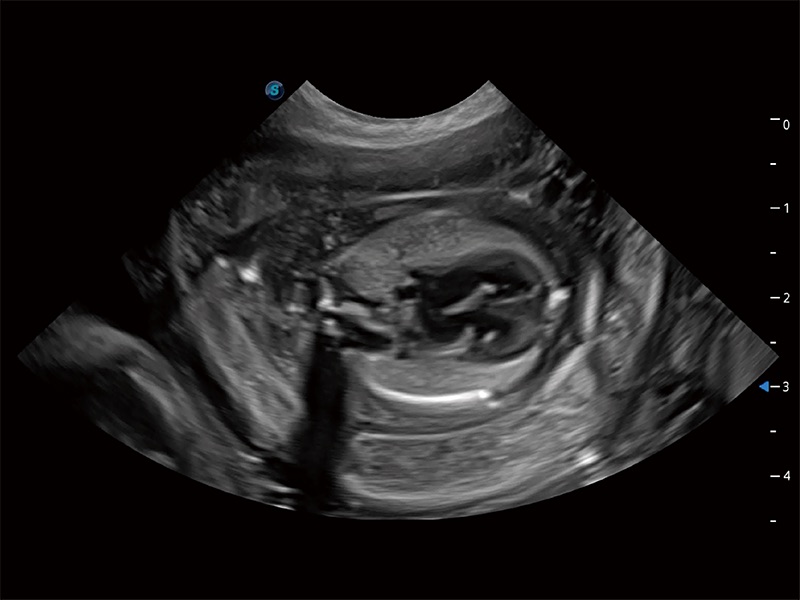

(犬)胎儿四腔心